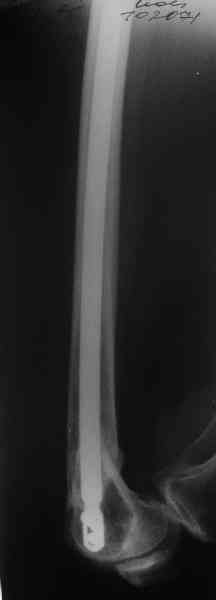

А в чем проблемы? Пример в приложении.

В приложении функциональные снимки в 3 мес. и в 1 год.